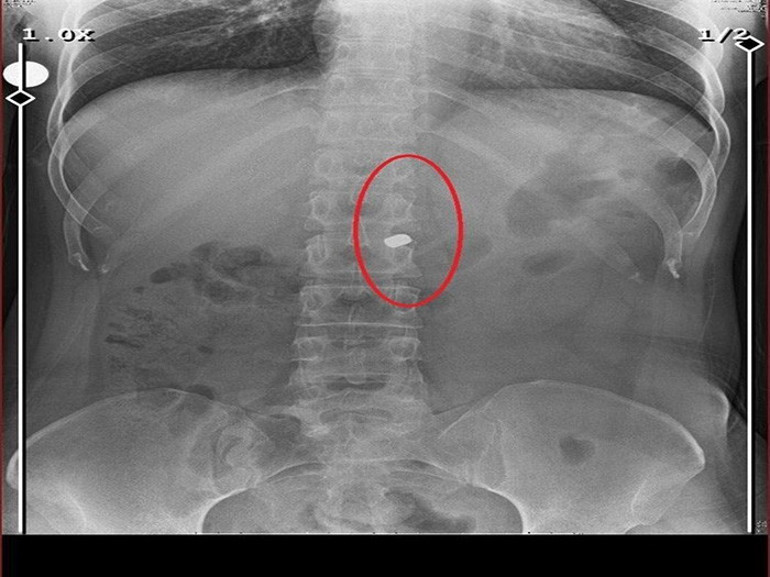

Eski sevgilisi tarafından 8 kurşunla vurulmuş olan ve vücudunda 2 mermi çekirdeği hala bulunan Fatma O., hayata tutunma çabası içinde olduğunu belirterek, “Bedenimdeki yaralar yeterince canımı yakıyor, bir de hayat yoruyor. Mendil satarak geçinmeye çalışıyorum. Kimseden yardım beklemiyorum fakat sadece bir işim olsun istiyorum. Kolum sakat, çalışamıyorum. Mendil satıyorum ama herkes beni dilenci sanıyor. Dilenci değilim; kimseyi aşağılamak istemiyorum, lütfen yanlış anlaşılmasın ama bunları hak etmiyorum” dedi.